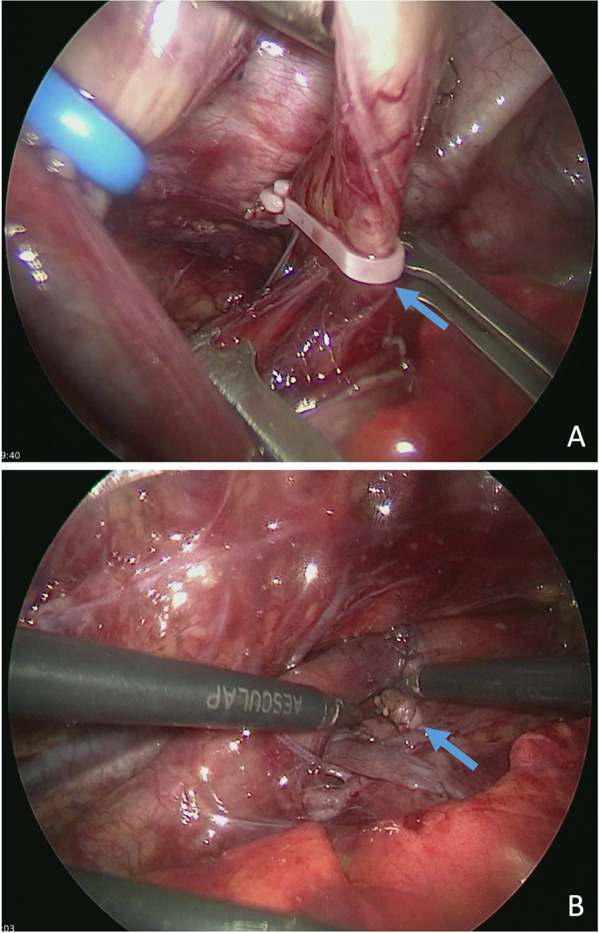

Case report: A term boy (GA: 42 + 1 weeks; BW: 3,110 g) underwent thoracoscopic TEF repair for Type C EA. We ligated the fistula using a polymer clip followed by primary esophageal anastomosis on the second day of life. At ten weeks of age, we readmitted the infant due to recurrent bronchitis and episodes of postprandial coughing. Flexible bronchoscopy revealed that the polymer clip, previously employed for fistula closure, had migrated into the right main bronchus and was subsequently retrieved. Despite clip removal, persistent coughing prompted further evaluation, revealing a recurrent TEF on contrast esophagography. An interdisciplinary team successfully obliterated the recurrent fistula using endoscopic chemocauterization with trichloroacetic acid (TCA) via rigid bronchoscopy. Additionally, due to a developing anastomotic stricture, the patient required four balloon dilations and a single triamcinolone injection. At the three-year follow-up, the patient is eating well and thriving normally.